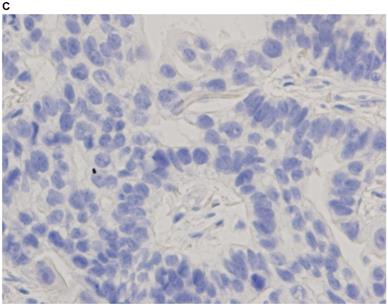

Representative images of PD-L1 immunohistochemistry staining of tumor cells obtained via EBUS-TBNA and TBB are shown in Figure 2.

Figure 2

Immunohistochemistry characterization. Representative images of programmed death ligand-1 immunohistochemistry staining of tumor cells obtained via endobronchial ultrasound-guided transbronchial needle aspiration (A tumor proportion score [TPS] ≥50%, B TPS = 1‒49%, C TPS <1%) and transbronchial biopsy (D TPS ≥50%, E TPS = 1‒49%, F TPS <1%) (40x magnification).